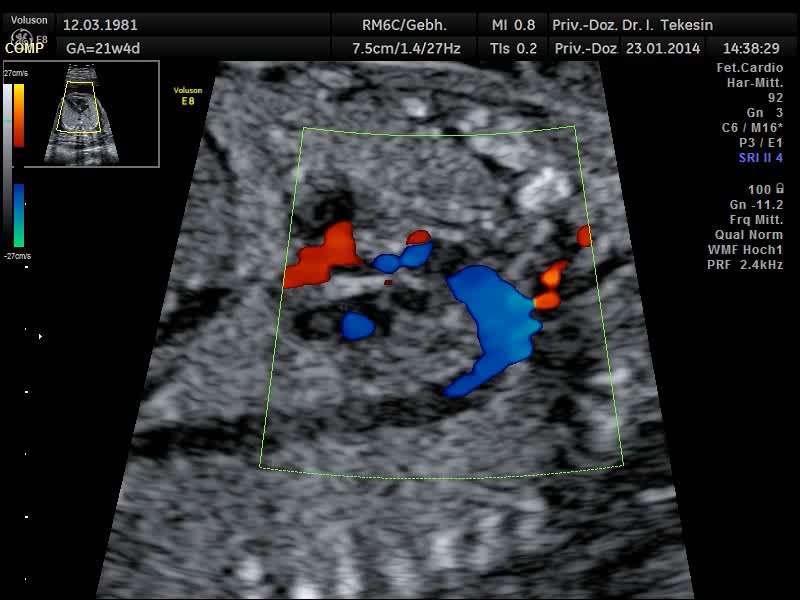

Normaler Vierkammer–Blick mit Farbe

Normaler Vierkammer-Blick mit Farbe